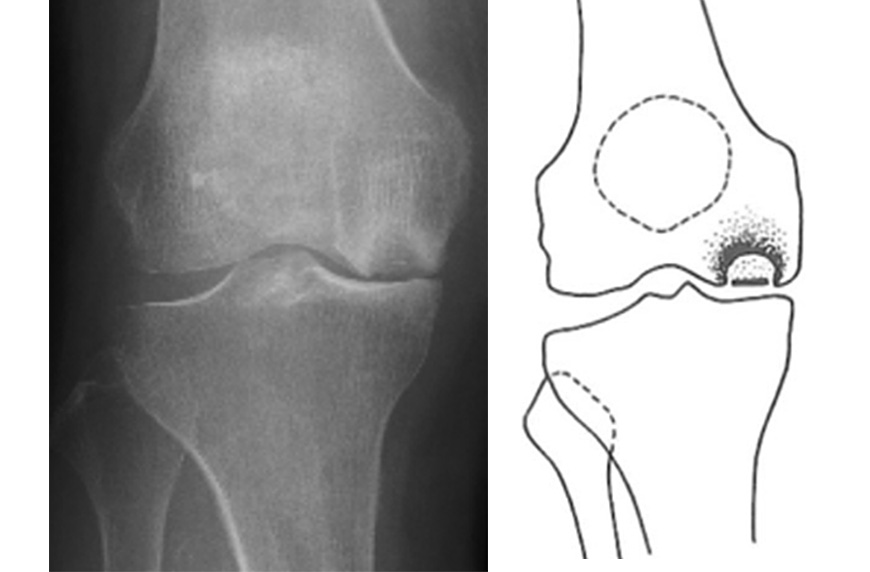

●膝関節特発性骨壊死

骨壊死とは骨の内部が傷んで、組織が死んでしまっている状態を指します。「特発性」とは、原因がわからないものという意味ですが、当初は大腿骨頭壊死という血流途絶の影響が懸念されていました。

しかし近年では、半月板損傷が84%に合併しており、半月板断裂や半月板が逸脱する事での過剰負荷と考えられています。

このような状態まで進んでしまうと、O脚になったのちに変形性膝関節症に進行してしまいます。 膝の治らない痛みで徐々に悪くなっていく事が特徴的です。